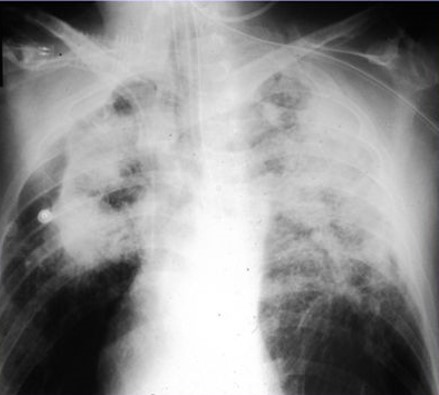

Workers fabricating artificial stone countertops, also known as engineered or Quartz, made from crystalline silica and resin, face a severe risk of silicosis, a serious lung disease. Its high nano- sized silica content, up to 95%, is much greater than that of natural stones, making it particularly hazardous. The fabrication processes, including cutting, grinding, and polishing, release dangerous silica dust into the air. Wet sawing, ventilation, and protective gear are insufficient to prevent inhalation of the harmful particles. Historically, silicosis would take decades to develop with natural stone, but with artificial stone, symptoms usually appear in just a few years. Workers affected by such exposure, including undocumented immigrants, are urged to seek legal assistance from Brayton Purcell LLP.

Asbestos has been used in thousands of products and in numerous workplaces. By the early 1900s, scientists and medical professionals began noticing a large number of early deaths and lung problems in asbestos mining towns and asbestos cloth factories. Great Britain made asbestosis a compensable work-related disease by the 1930s; the U.S. followed about 10 years later.

By 1928, it was well established in medicine, science and industry that asbestos dust released from any asbestos-containing product caused asbestosis; by 1944 lung cancer; by 1960 mesothelioma; and by 1965 various other cancers. Yet, asbestos was not removed from most products until the 1970s and 1980s, and remains in some products even today.